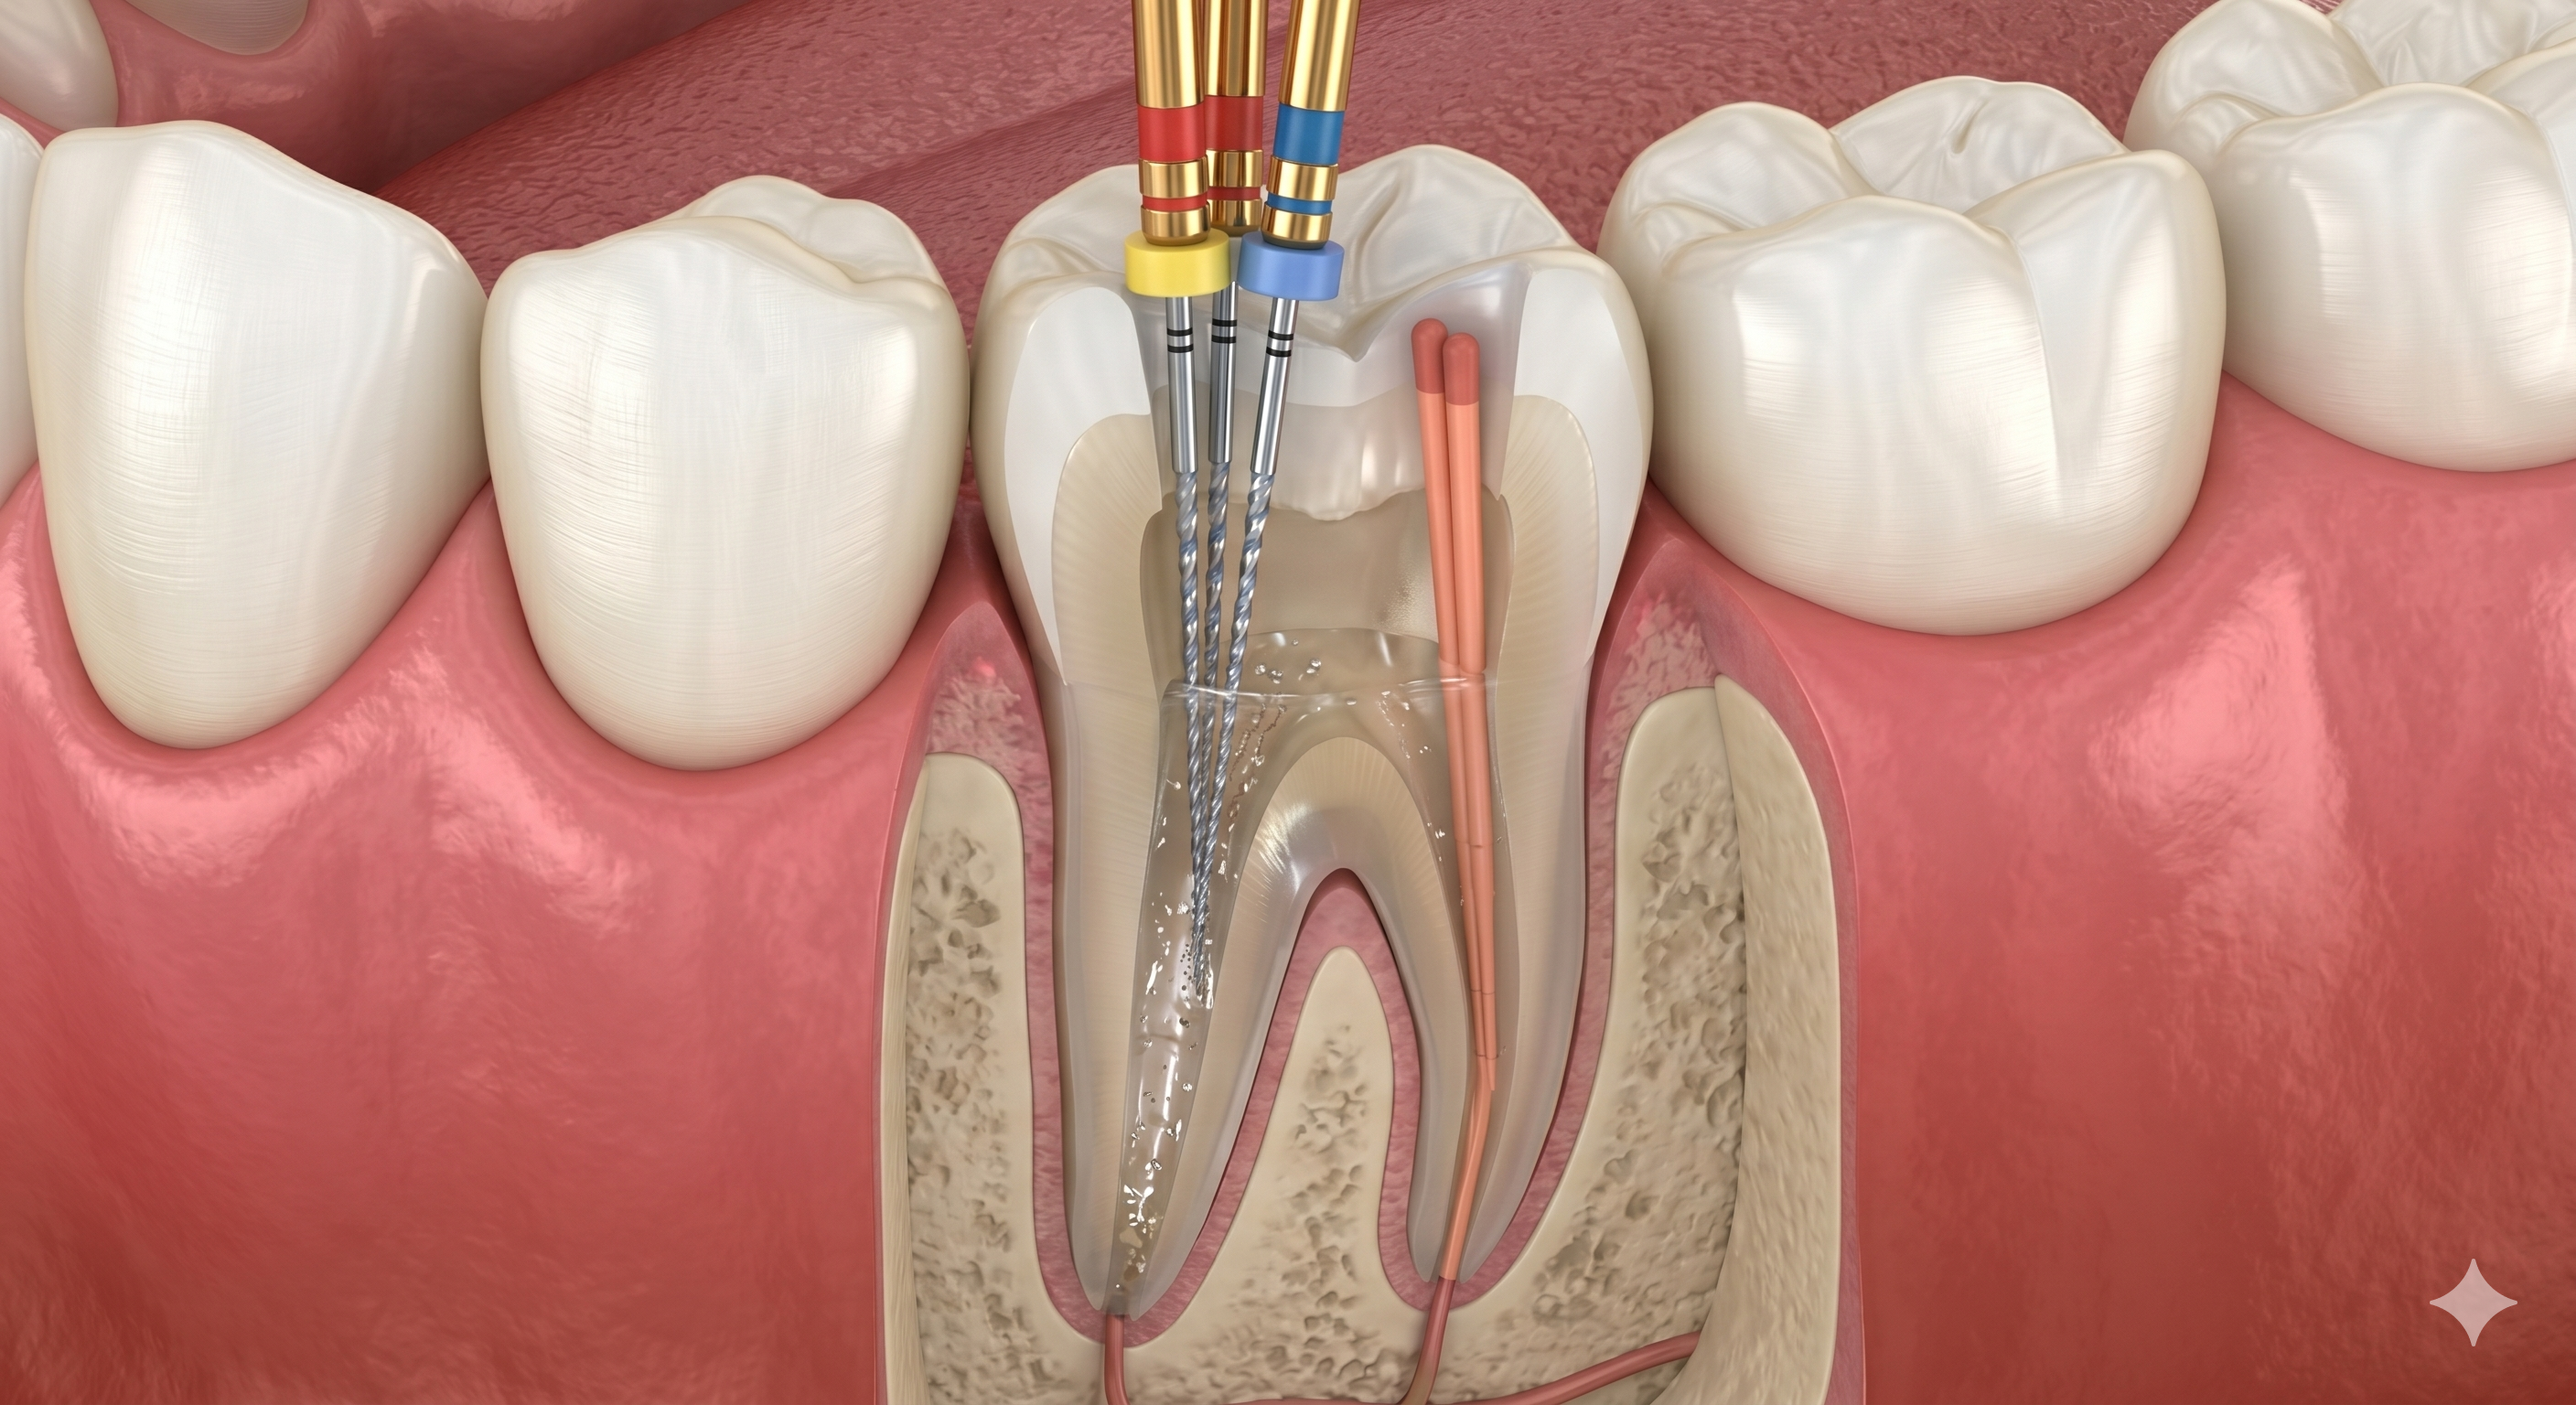

Endodontic

Our Root Canal Treatment is a highly precise procedure aimed at saving teeth that would otherwise need extraction. We effectively remove infection from the inner canals to provide immediate relief and long-term tooth preservation.